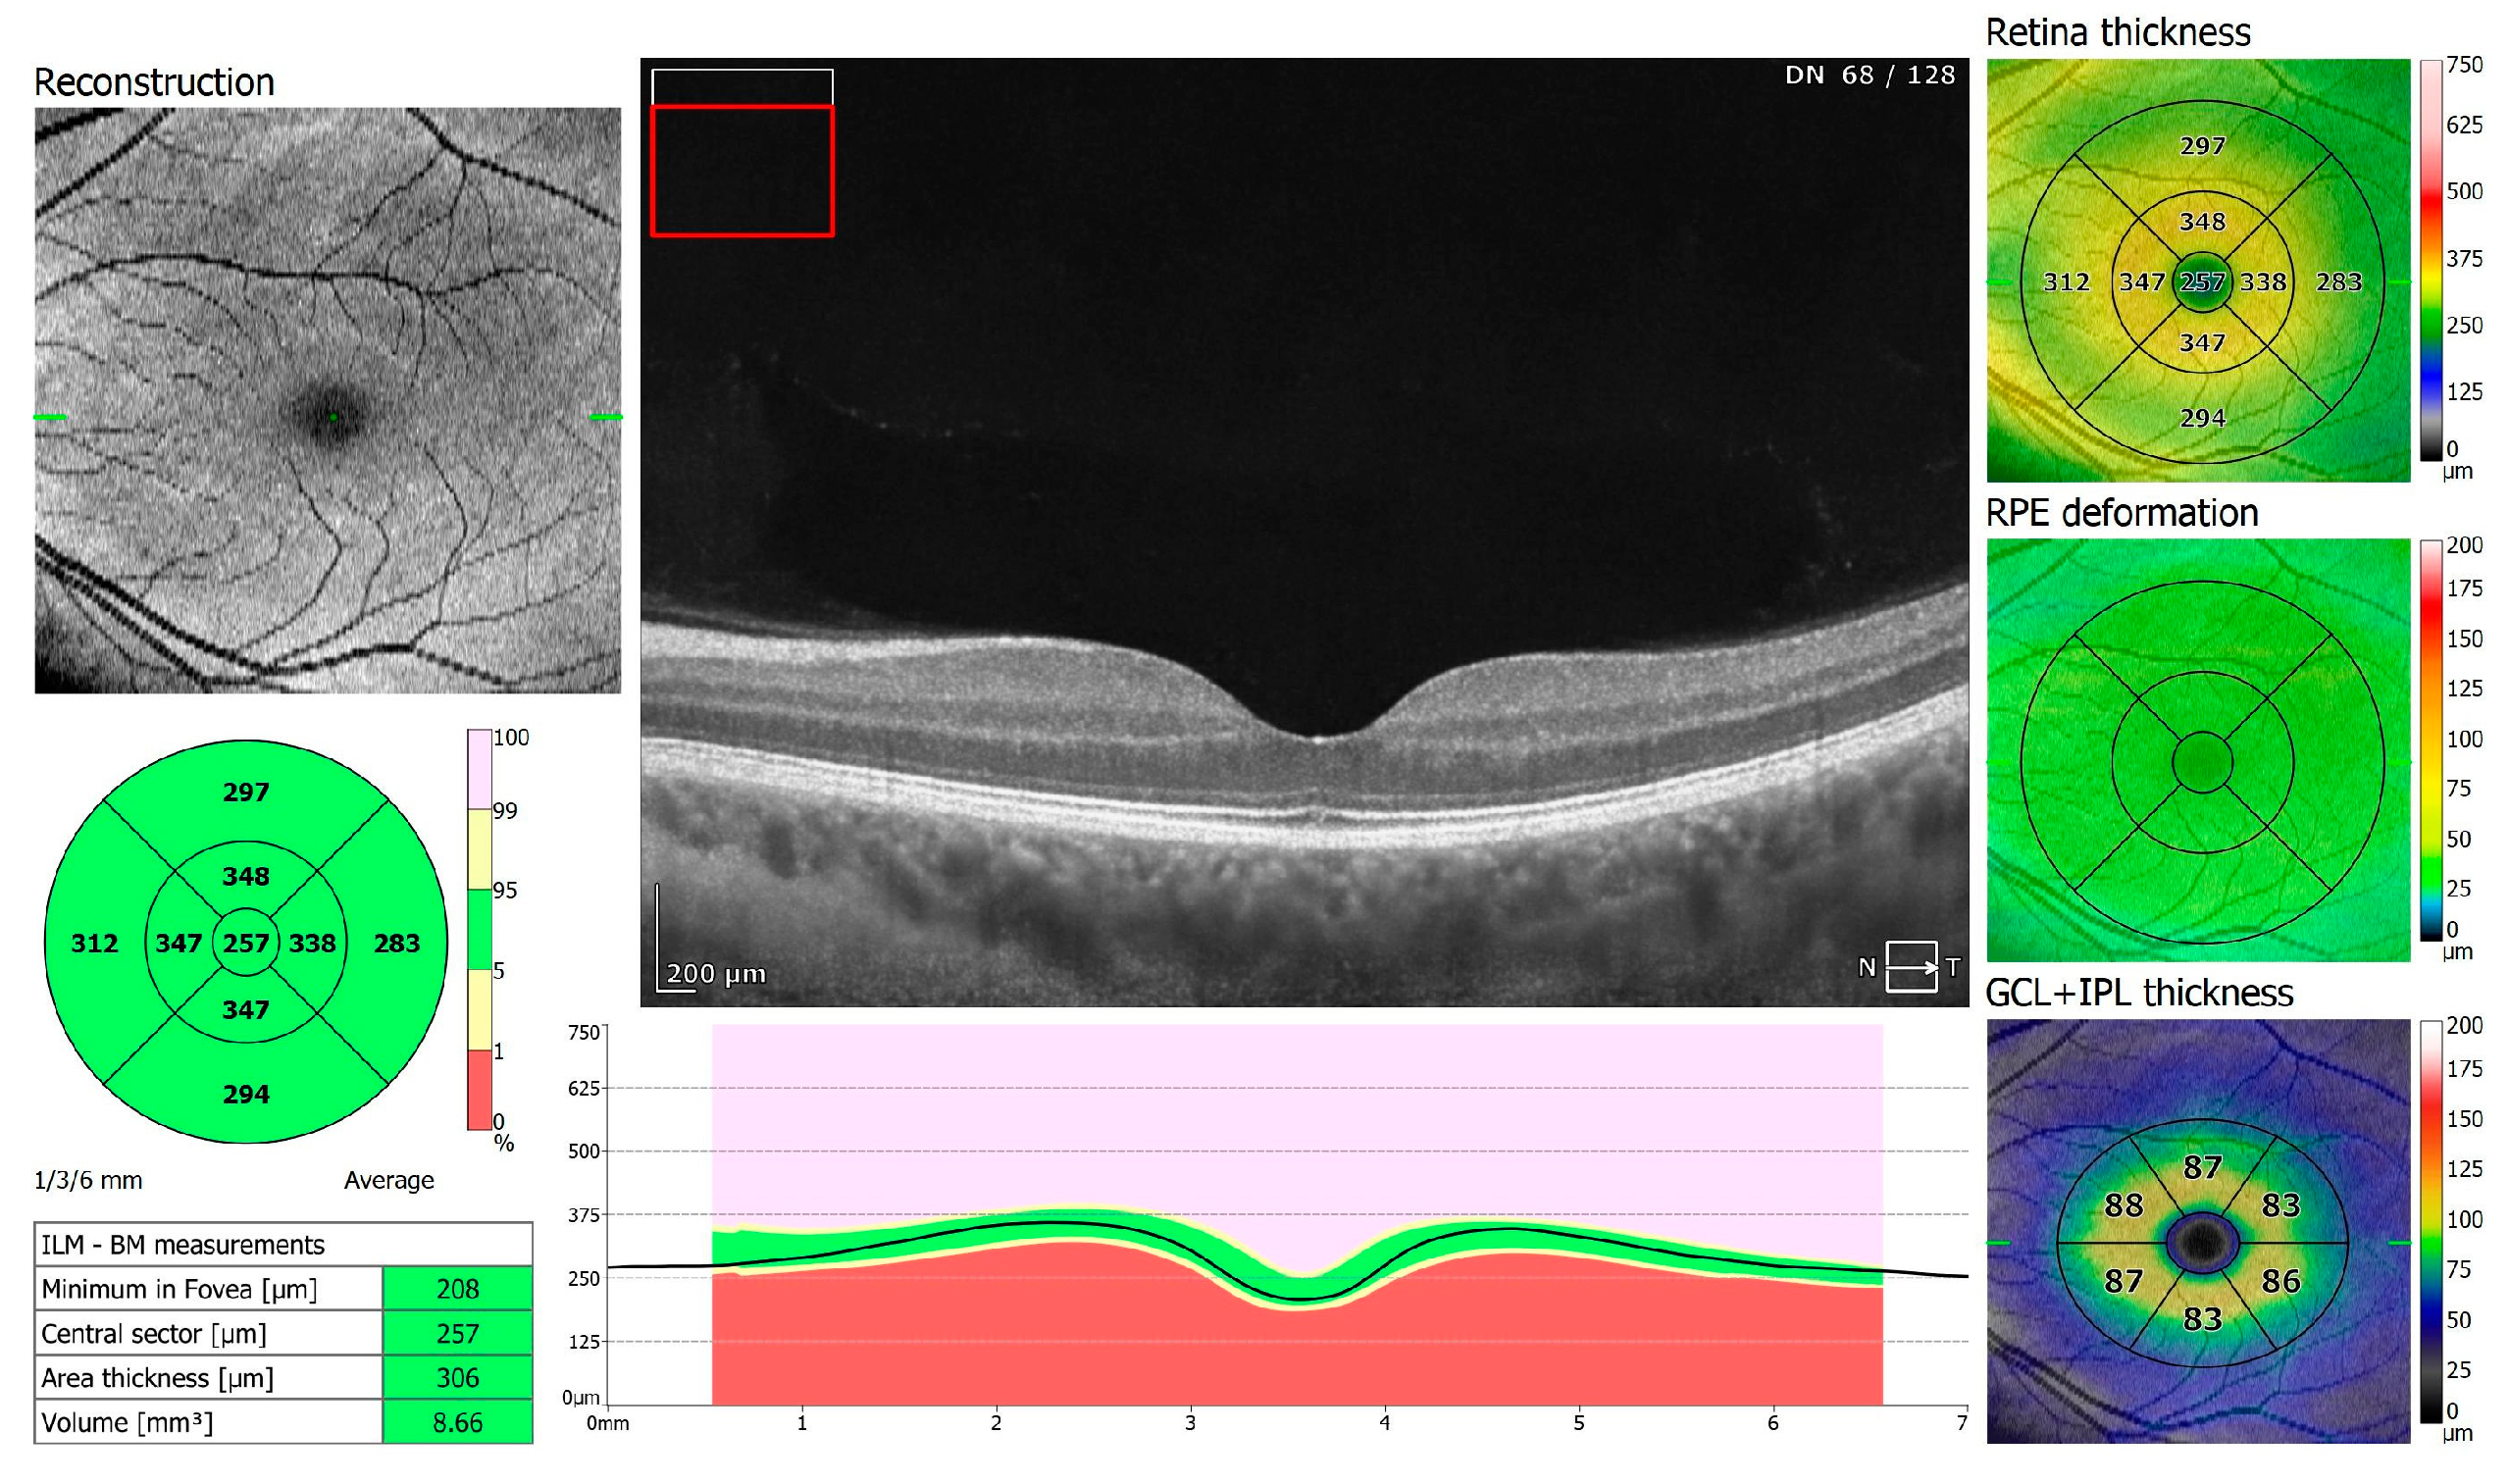

Figure 2.

OCT 3D macula scan 7 × 7 mm of COVID-19-negative patient. RPE, retinal pigment epithelium; GCL + IPL, ganglion cells layer + inner plexiform layer; ILM–BM, inner limiting membrane–Bruch’s membrane.

Of the participants, 20 received oxygen therapy at flow rates ranging from 1–10 L, while 4 received high-flow intranasal oxygen therapy (HFNOT). Additionally, 5 patients were treated with Remdesivir therapy, 5 received COVID-19 convalescent plasma therapy, and 11 were treated with Tocilizumab. The demographics and clinical characteristics of the study participants are presented in Table 1. The mean time from a positive PCR test to study enrollment was 13.23 days, with a standard deviation of 8.18 days. The control group comprised 38 healthy individuals: 28 men and 10 women (control versus research group: p = 0.21), with an average age of 58 years, ranging from 33 to 69 years. All participants underwent two examinations, one upon admission and another upon cessation of therapy (6.70 ± 6.46 days). Spectral-domain optical coherence tomography (SD-OCT) was conducted using REVO FC 130 (Optopol Technology, Zawiercie, Poland). This device allows for high-resolution imaging and quantitative analysis of both the retina and cornea. The study specifically evaluated central retinal thickness, retinal nerve fiber layer (RNFL) thickness and optic disc parameters, alongside central corneal thickness and corneal epithelium thickness. The measurements were performed using built-in retinal and corneal layer segmentation tools provided by the OCT system, which automatically segmented the different layers of the retina and cornea to ensure precise and repeatable thickness measurements. OCT protocols included a 3D macula 7 × 7 mm scan, 3D disc 6 × 6 mm scan, and anterior radial 8 × 8 mm scan (Figure 1, Figure 2, Figure 3, Figure 4, Figure 5 and Figure 6). All patients had also undergone slit lamp examination, including indirect ophthalmoscopy.